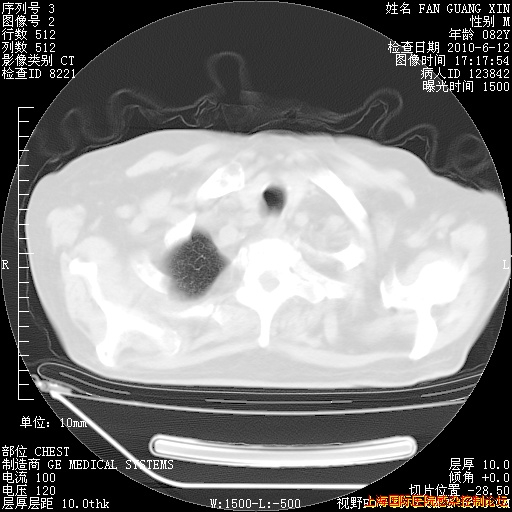

6月12日纵膈窗

整整相隔30天的肺部CT好像有所好转啊。甲强龙减量第3天,需要观察体温。